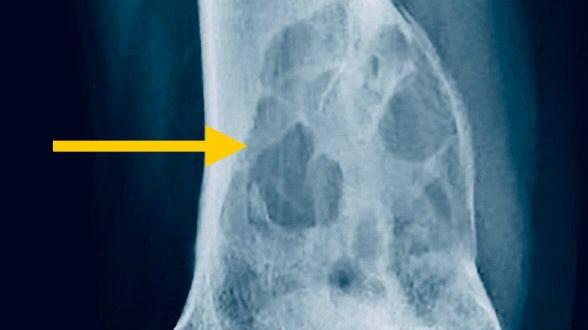

骨巨細胞瘤

「侵侵」骨骼的骨巨細胞瘤